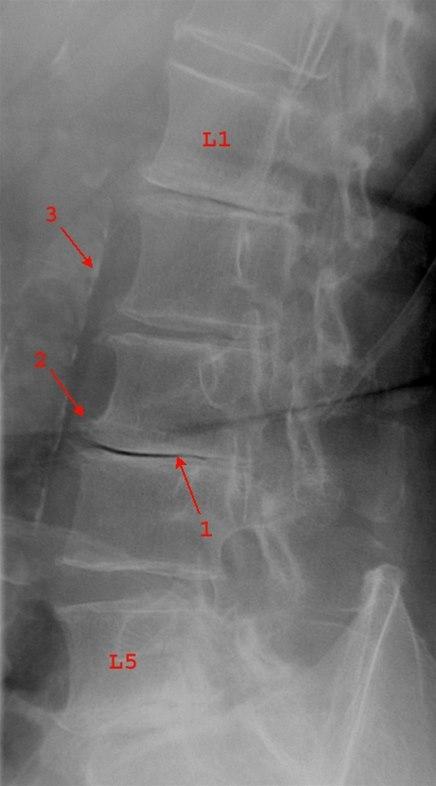

Redusert skivehøyde i alle lumbale nivåer unntatt L4/L5

Svært lav skive med vakuumfenomen L3/L4 (1). Lette til moderate randpåleiringer (2)

Bifunn: Veggforkalkninger i aorta